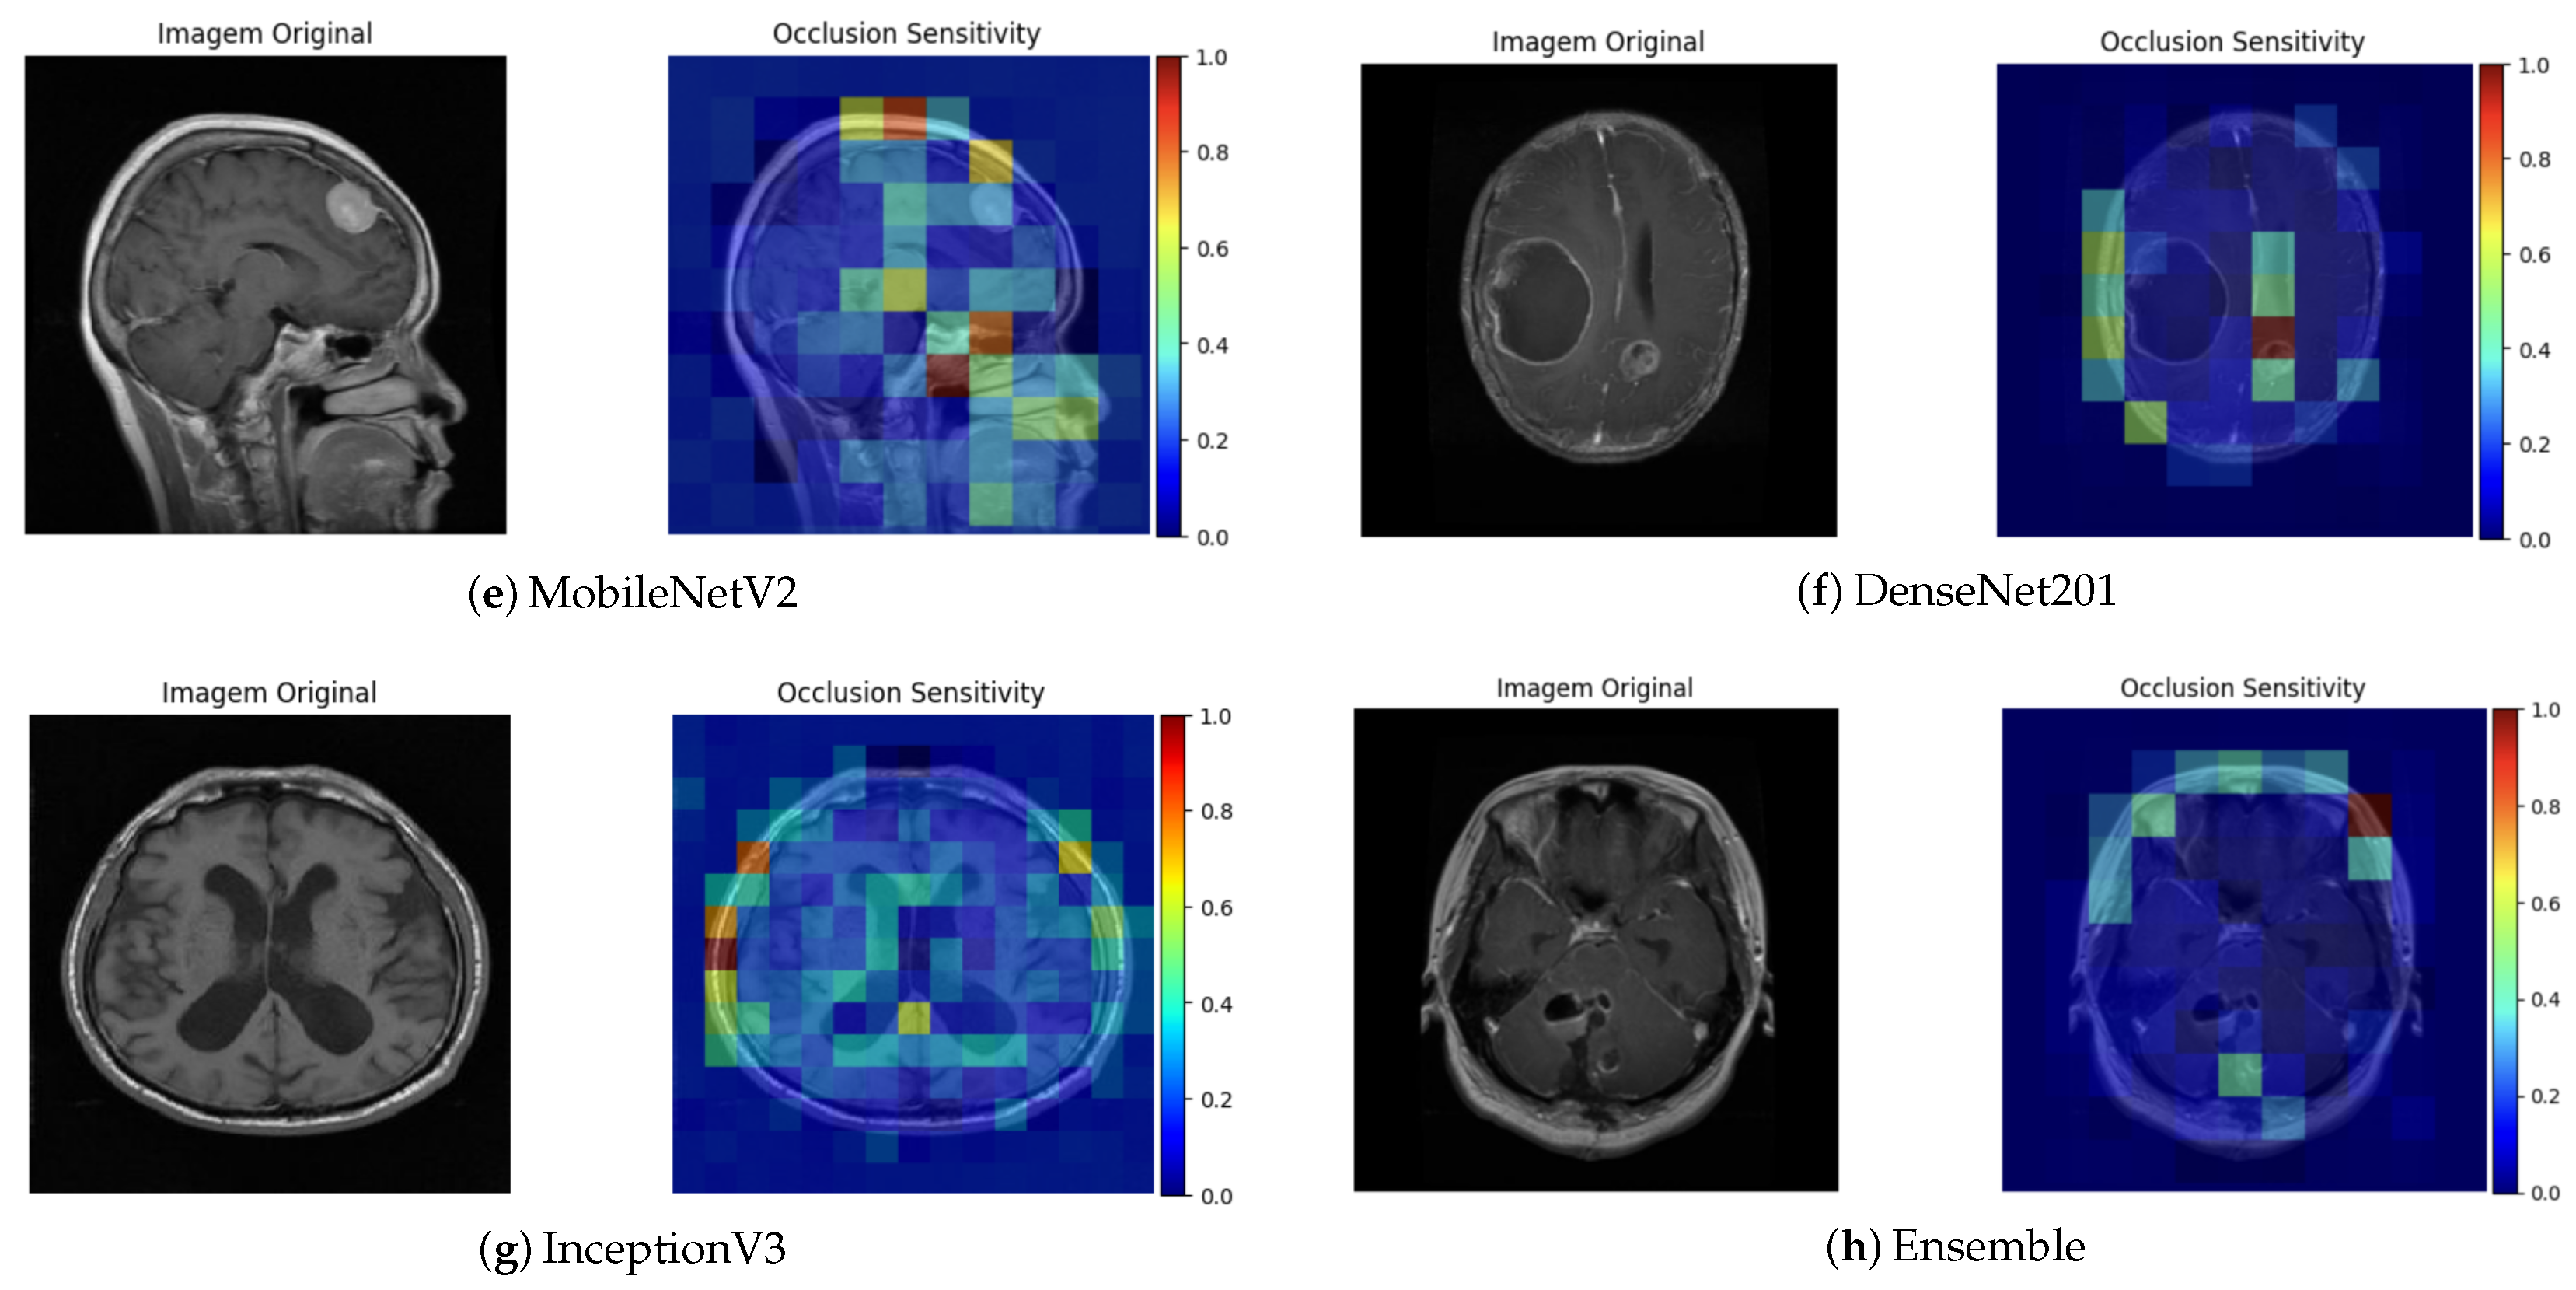

The Occlusion Sensitivity technique complements this analysis by measuring the variation in prediction confidence when different parts of the image are occluded. As shown in the figures associated with this technique (Figure 9), a significant reduction in the probability of classification was observed when the tumor region was partially hidden. This behavior indicates that the model strongly relies on that area for its decision, which supports consistency between the reasoning of the network and the relevant clinical anatomy.

Figure 9.

Occlusion Sensitivity visualization for different architectures.